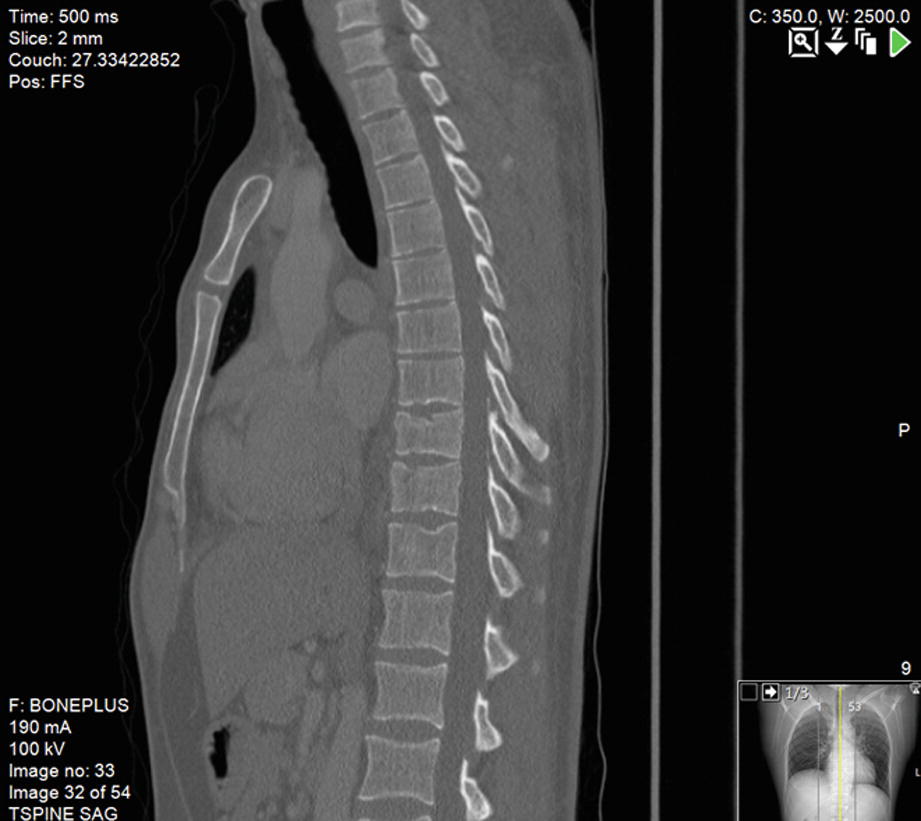

Wedge fracture treatment uk. This is a type of fracture where the vertebrae building blocks of. You will have either a crush biconcave or. The choice of treatment should be made on an individual basis after discussion. Have uncontrolled pain. The first step is to properly diagnose and localize the fracture using a combination of clinical symptoms and imaging such as an x-ray CT scan or a MRI. KYPHOPLASTY USING BALLOONS OR STENTS The objective of this technique is to relieve.

The fracture can also be caused by cancer osteoporosis and any number of other conditions. A patient who has sustained one fragility fracture is at high risk of experiencing secondary fractures especially. A spinal fracture is when a bone in your spine becomes compressed or squashed after losing strength. Osteoporosis itself is asymptomatic and often remains undiagnosed until a fragility fracture occurs. Treatment of a Wedge Fracture Whether someone sustained their wedge fracture falling out of a free or in a pedestrian injury the treatment process typically begins in the same way. Osteoporosis - prevention of fragility fractures.

It is associated with a 15 higher mortality rate. Spinal fractures are a common consequence of osteoporosis. A sub-type of the Compression Fracture is a Wedge Fracture. Fragility fractures which result from low energy trauma such as a fall from standing height or less are a sign of underlying osteoporosis. Osteoporosis is a disease characterized by low bone mass and structural deterioration of bone tissue with a consequent increase in bone fragility and susceptibility to fracture. The spine caves in on itself due to compression or pressure on the bone.

Lumbar Spine Thoracic Spine. The links below explain more about spinal fractures including their. If you suffer from Wedge Fractures or broken vertebrae Deuk Spine Institute is here to help. Anterior Wedge Fracture to the Vertebra. TREATMENT OPTIONS SPINAL FRACTURES MINIMALLY INVASIVE TREATMENTS VERTEBROPLASTY The aim of this technique is to stabilise the fracture and relieve pain. These fractures are usually stable and do not cause any short or long term paralysis.

Surgically treating wedge fractures includes restoration of vertebral height and providing spinal column stability using instrumentation and fusion. Its not the same as a broken back so be reassured it doesnt lead to a risk of being paralysed. Stability is ultimately achieved by spontaneous anterior fusion or surgical fusion. The preferred mode of treatment for Wedge Fractures is braces which need to be worn for around 10-12 weeks for immobilization and allowing the bones to heal. 4 Furthermore the estimated annual medical cost of VCF management in the UK was approximately 147 million. The fractured vertebrae are stabilised by injecting bone cement into the centre of the vertebra.